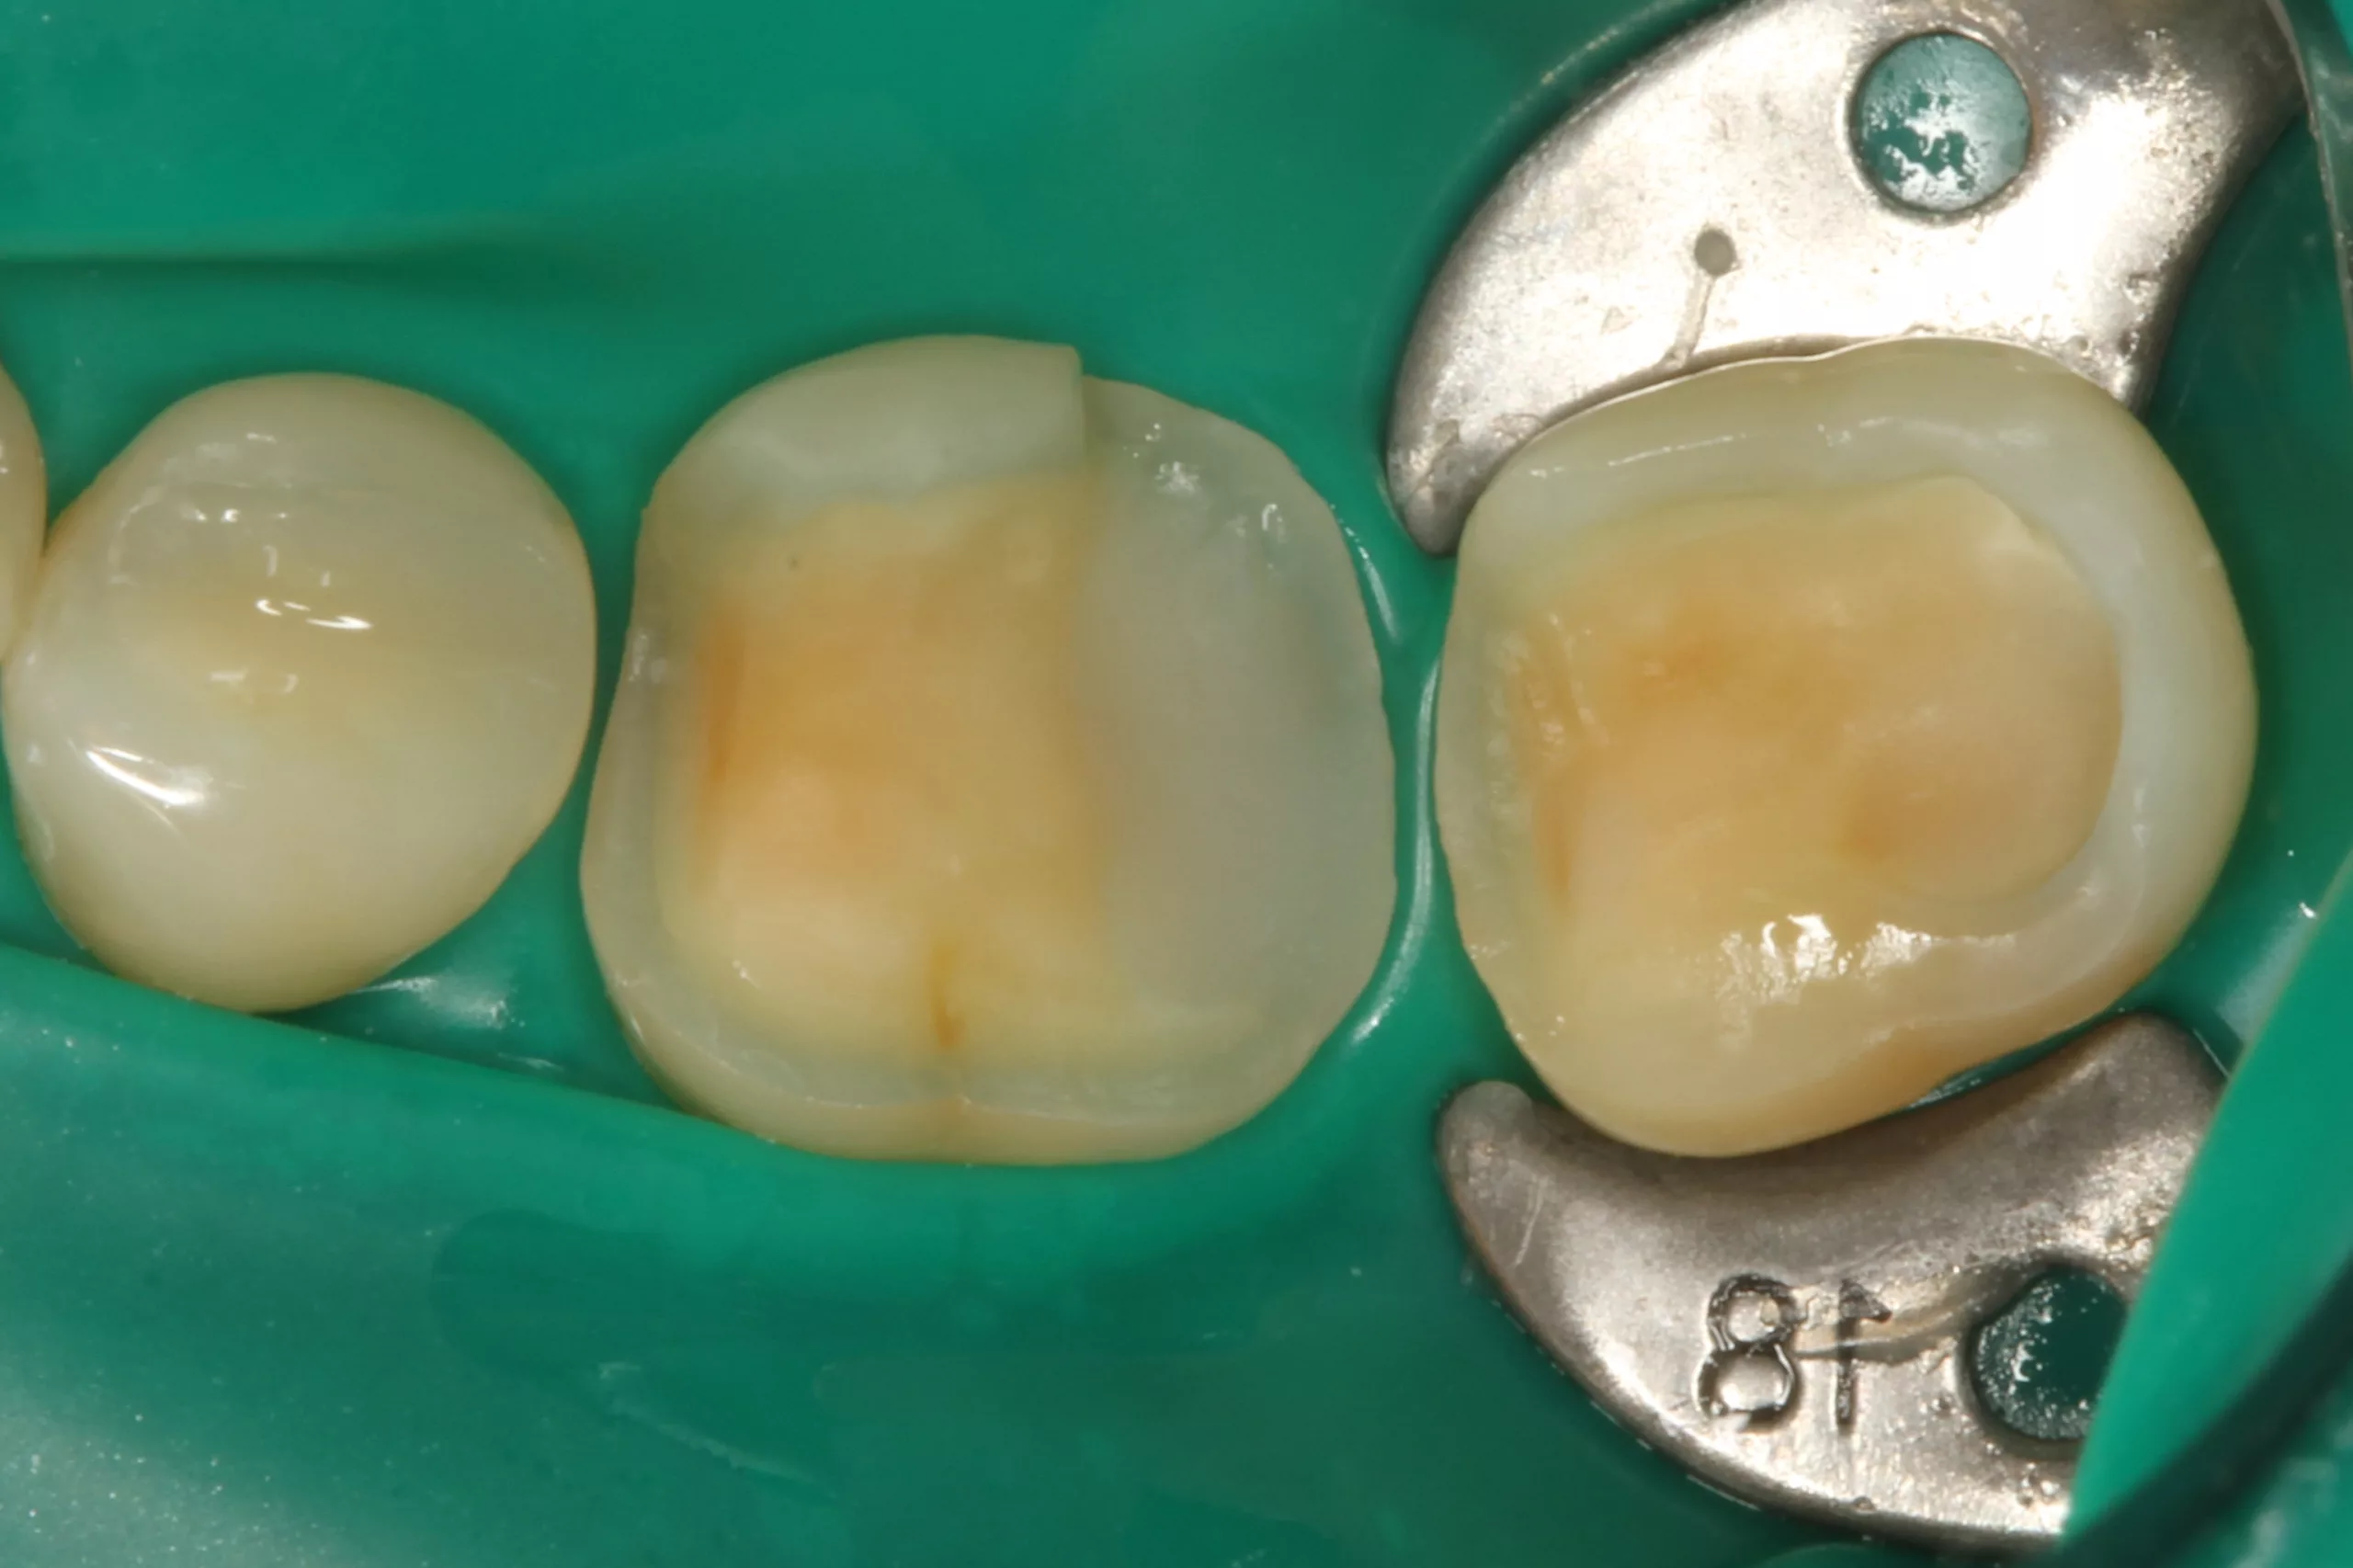

Weiter geht es am Zahn: Die Kontaminationskontrolle ist bei der adhäsiven Befestigung essenziell [84]. Das einfachste Tool – gerade bei adhäsiven Teilkronen – ist die Kofferdamisolierung. Die Abbildung 2 zeigt den isolierten Arbeitsbereich nach Entfernung der Provisorien, der Reinigung der Klebeflächen mit Ultraschall und Bims-Paste (Zircate, Dentsply Sirona) sowie dem Abstrahlen der Kompositfläche an Zahn 46 mit 50 ?m Aluminiumoxid (Rondoflex, KaVo). Die kurze, flügellose Molaren-Kofferdamklammer erleichtert den Zugang zum Approximalraum bei der Versäuberung mit Zahnseide. Da es sich in diesem Bereich um eine adhäsive Kavitätenbodenelevation mit Komposit [66] im Vorfeld der Präparaton und nicht um eine adhäsive Aufbaufüllung handelt, kommt der suffizienten Vorbehandlung auch dieser Klebefläche eine entscheidende Bedeutung zu, um einen Haftverbund zwischen dem Komposit und dem adhäsiven Befestigungssystem zu gewährleisten.

Nach der Schmelzkonditionierung mit dem Phosphorsäuregel und dem ausreichenden Spülen für 15 Sek. ist für eine suffiziente volladhäsive Anbindung ein Benetzungsmittel, ein „Tooth Primer“ erforderlich. Der zu Visalys CemCore gehörende Visalys Tooth Primer ist ein selbstkonditionierender Einkomponenten-Primer, der keiner separaten Lichthärtung bedarf und somit die Ansprüche an die Selbsthärtung des Adhäsivs, die anschließend im Kontakt mit Visalys CemCore abläuft, erfüllt. Die Abbildung 3 zeigt die Einwirkung des Visalys Tooth Primers auf die Präparationsflächen der beiden Zähne 46 und 47. Die Befestigung der Teilkronen erfolgte gleichzeitig mit Visalys CemCore in der Farbe Universal (A2/A3), das vorab direkt auf die Teilkronen und nicht in die Kavitäten appliziert wurde (Abb. 4). Obwohl eine „Tack Cure“-Technik-Option zur Verfügung steht, wurden die Überstände des Befestigungsmaterials mittels Modellierspatel, frischem Bondingpinsel und Zahnseide entfernt. Die im Vergleich zu herkömmlichen Befestigungskompositen etwas höhere Konsistenz und bessere Standfestigkeit (kommt primär der Funktion als Stumpfaufbaukomposit zugute) erleichtert die Überschussentfernung immens, da das Material nicht so schnell unkontrolliert wegfließt. Es erfolgte eine initiale Härtung mittels eines Hochleistungs-LED-Polymerisationsgerätes. Zur Verhinderung der Sauerstoffinhibitionsschicht kann jedes herkömmliche Glyceringel verwendet werden. Alternativ kann die ebenfalls von Kettenbach angebotene Visalys CemCore Try In-Paste zur Anwendung kommen. Obwohl Visalys CemCore eine ausgezeichnete Selbsthärtung aufweist, erfolgte dennoch eine Lichthärtung unter Glyceringel für 20 Sek. pro Fläche. Die Überprüfung der statischen und dynamischen Okklusion darf erst nach Abschluss der Dunkelhärtung vorgenommen werden, damit die adhäsive Integration nicht gestört wird, wenn im Polymerisationsprozess durch Exkursionsbewegungen mechanisch auf die Klebefläche eingewirkt wird.